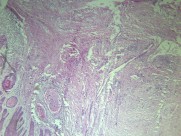

鳞癌是鳞状细胞癌(squamous cell carcinoma)的简称,常发生在身体原有鳞状上皮覆盖的的部位,如皮肤、唇、口腔、食管、喉、子宫颈、阴道、阴茎等处。有些部位如支气管、胆囊、肾盂等处,鳞状细胞癌:高分化,可见角化珠正常时不是由鳞状上皮覆盖,但可通过病理演变鳞状上皮化生…